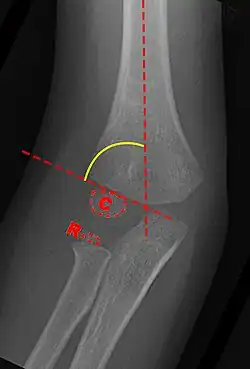

Baumann's Angle

Carrying angle can be evaluated through AP view of the elbow by looking at the Baumann's angle.[3] There are two definitions of Bowmann's angle:

The first definition of Baumann's angle is an angle between a line parallel to the longitudinal axis of the humeral shaft and a line drawn along the lateral epicondyle.

Another definition of Baumann's angle is also known as the humeral-capitellar angle. It is the angle between the line perpendicular to the long axis of the humerus and the growth plate of the lateral condyle. Reported normal values for Baumann's angle range between 9 and 26°.[7] An angle of more than 10° is regarded as acceptable.[7]